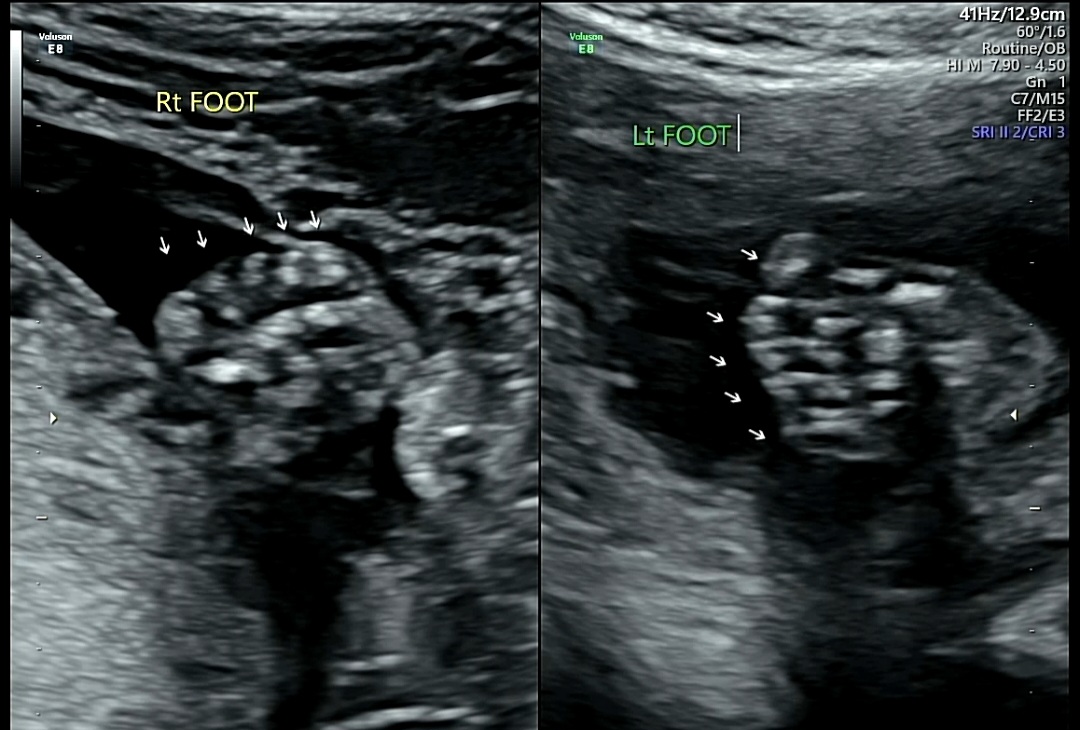

3) Lt HAND(왼쪽 손)/Rt Hand(오른쪽 손)/Lt FOOT(왼쪽 발)/Rt FOOT(오른쪽 발)

양쪽 손가락, 발가락 모양 및 개수 확인

꿀떡이가 주먹을 쥐고 있는 바람에 손가락 개수 세는 것도 쉽지 않았다.